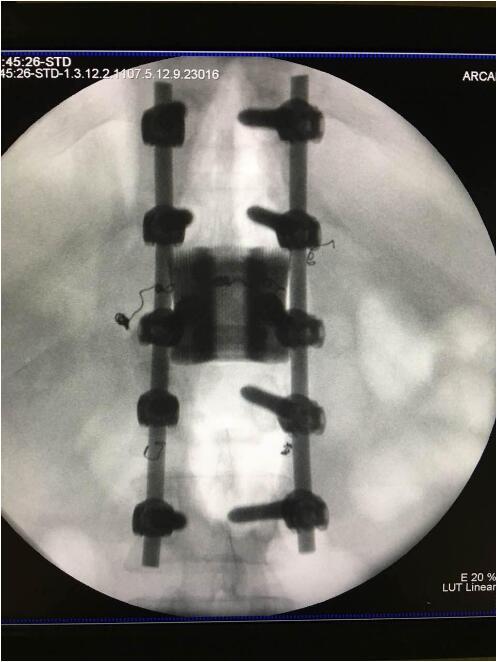

这次手术是广州华钛三维骨科研究中心(华钛三维骨科研究院)与南方医院联合澳大利亚技术科学与工程院吴鑫华院士领导的莫纳什大学增材制造研究中心合作的世界第一例3D打印个性化"人工椎体/腰间盘一体化"植入手术。南方医院脊椎及骨病外科郑明辉副主任医师在岭南名医陈建庭主任和朱青安教授指导下,与华钛三维工程师陆国赞合作构思设计,澳大利亚莫纳什大学增材制造研究中心主任吴鑫华院士团队进行了一个多月的个性化钛合金3D打印工艺研究,成功打印出符合病人要求的人工椎体/腰间盘一体化"植入物。这次手术的成功,标志着中国的3D打印植入物技术在骨科医疗领域达到世界先进水平。

为了更好的完成手术,陈建庭主任、郑明辉副主任医师等骨科专家与华钛三维的3D打印专家从2017年10月份开始筹备该手术。考虑到每一个病人的脊椎形状都存在差异,骨科专家认为用一个现成的标准植入物不大可能匹配病人的生理参数。医学专家和3D打印专家根据病人脊柱的CT扫描数据,为病人的脊柱建立了精准的3D图像。根据这个图像,治疗团队就能够设计并定制出属于病人的个性化植入物。为了使个性化定制的人工椎体与病人椎体之间更好的融合,手术实施前治疗团队先后设计了100多个方案,制作了数十个植入物的术前模型进行研讨。事实证明,手术最终使用的植入物是最适合手术和病人身体情况的。

利用3D打印技术生产出来的人工椎体是完全按照患者的解剖结构完成脊椎结构重建及固定的, 装上一枚精准的、个性化的人工脊椎,患者康复后完全可以正常地生活和工作。过去这种手术常常是使用钛网内填入自体或异体碎骨作为椎体间支撑材料,但钛网一旦移位压迫脊髓,患者就会有瘫痪的风险。这次手术中的脊椎植入物内部具有经过力学优化设计的晶格结构,比传统钛网具有更强的承重力,金属3D打印可以直接制造出这样的复杂结构。

最终在经历近八个小时后,病人的家属终于等到了好消息:人工椎体/椎间盘一体化金属植入物成功植入,手术顺利。由于病人术中出血量小,生命体征平稳,他不用进入ICU观察,直接回到了普通病房。“现在我们都很高兴,成功做出了世界首例人工椎体/椎间盘一体化金属植入物,病人今后可以与常人一样工作和生活。”郑明辉医生说。